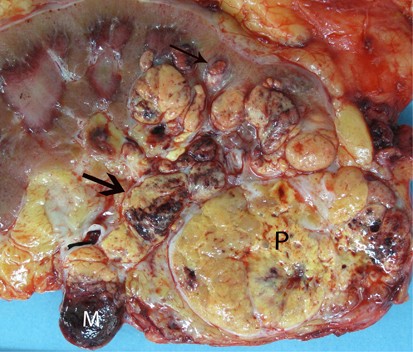

Figure 1

This clear-cell carcinoma invaded the inferior vena cava, the main renal vein (M) and sinus veins (large arrow). Nodules of retrograde venous invasion tumor are also present within the renal parenchyma (small arrow). P, primary tumor.